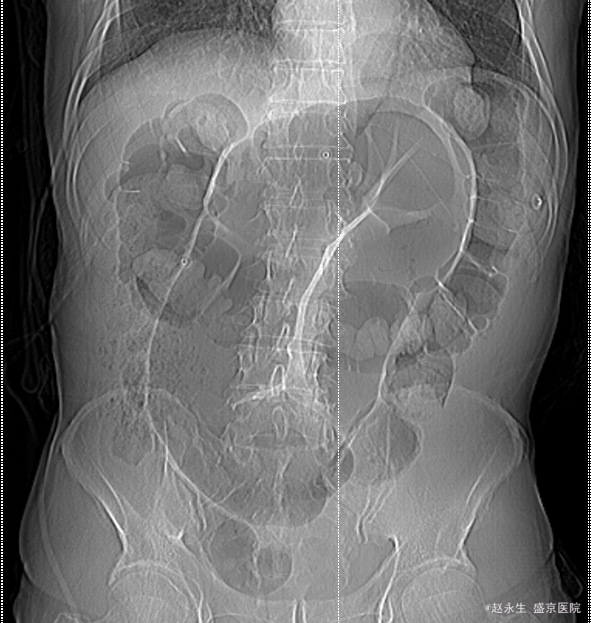

乙状结肠扭转1例

591x623 - 309KB - PNG